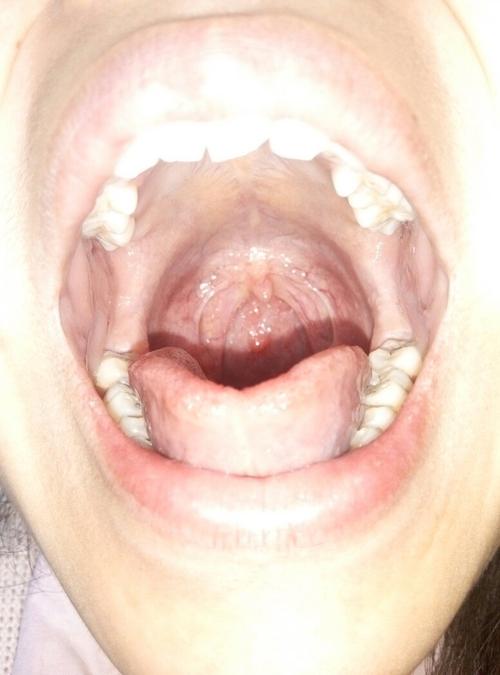

喉咙里面有小疙瘩

喉咙里面有小疙瘩,正常喉咙

正常喉咙

正常喉咙图片对比

喉咙正常与发炎图片

正常喉咙照片